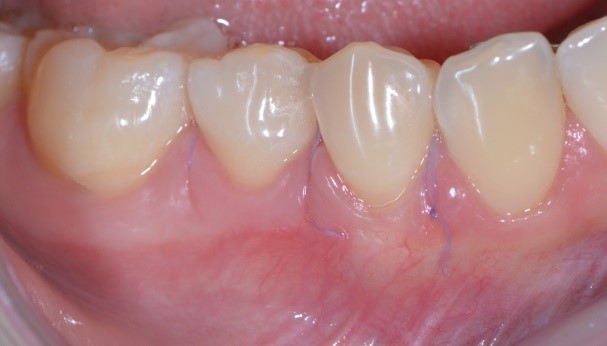

C’è un trucchetto di mezzo però. Devo confessarti che ho usato Photoshop, ma non per cambiare lo stato di salute dei tessuti (non saprei neanche come fare in verità!!) guarda qui cos’ho fatto…

gestione dei tessuti molli - aspetto dei tessuti molli 02

Ho semplicemente cancellato via i punti di sutura. Sì perché quello è proprio l’aspetto della guarigione a 10 giorni di un lembo a spostamento coronale multiplo con innesto di connettivo prelevato dal palato! Concorderai con me che è un intervento abbastanza “aggressivo”. Si deve scollare un lembo a spessore misto, sezionale le fibre muscolari, spostare coronalmente il lembo, prendere un pezzo di “gengiva” dal palato (qui di solito i pazienti rabbrividiscono) e ficcarla sotto il lembo.